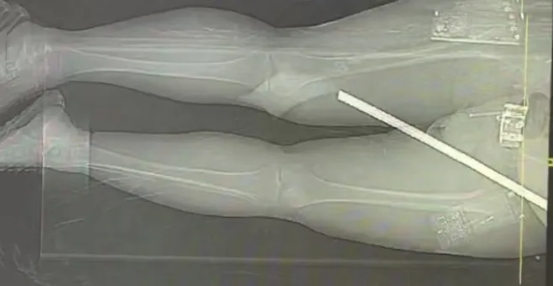

急诊与放射团队率先攻克检查难关。因钢筋两端外露,普通CT扫描孔径无法容纳,团队迅速将其转运至大孔径CT室。经过检查发现,钢筋从张先生右大腿后内侧穿入,沿髋臼及股骨颈后方斜行向上,从侧腰部穿出。万幸的是,钢筋未损伤其重要脏器,但与直肠、髂血管、坐骨神经等重要组织仅毫厘之隔。